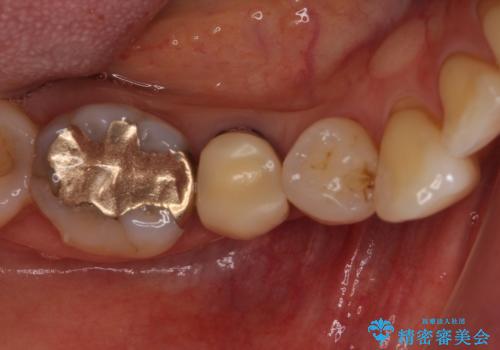

歯に穴があいた 奥歯のセラミック治療

- メインテナンスの際、以前よりものが挟まることが気になっていた患者様です。

神経が取り除かれた歯であるため、虫歯で歯が失われていく際に痛みを伴わなず、気がついたら大きな穴があいていました。

虫歯を全て除去したうえで新しい土台を築製し、セラミッククラウンにより補綴治療を行うこととしました。